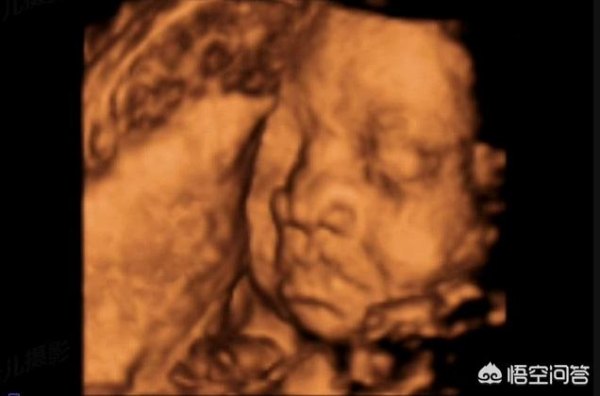

怀孕6个月时,胎儿长什么样子?

怀孕6个月,属于孕中期,此时胎儿发育速度加快,到孕24周为止,胎儿重约500-700g,长约28-30cm,像个葡萄柚一样大。

孕6个月,胎儿的头发、眉毛、睫毛越发清晰,身体看上去很匀称,只是皮下脂肪很少,仍然很瘦小,皮肤也特别薄,可以清晰的看到皮肤下的血管,骨骼,内脏。别担心,从此时起,胎儿的皮肤表层开始附着一层白色的胎脂,保护皮肤,同时随着孕期增加,皮下脂肪也会慢慢堆积,胎儿会变得越来越丰满。

记得之前有人发了一张胎宝宝大排畸的照片,小手在比耶,萌爆了哈。胎宝宝到6个月有大排畸产检,所以准爸妈们也都会非常期待看见宝宝的样子。

医学上界定6个月为孕24周,此阶段宝宝的体重约600g,身长30cm左右。子宫位置大概在肚脐上方3.8-5.1cm处。 胎宝宝的双顶径大约为6.05士0.50cm,腹围18.74士2.23cm,股骨长度4.36士0.51cm。

从B超中能看到这个时期胎宝宝轮廓已经很清晰了,五官都发育了,比例也越来越好,如果有照片或者视频,还可以大概看出来宝宝像妈妈还是爸爸。